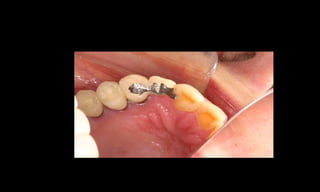

Cone Morse